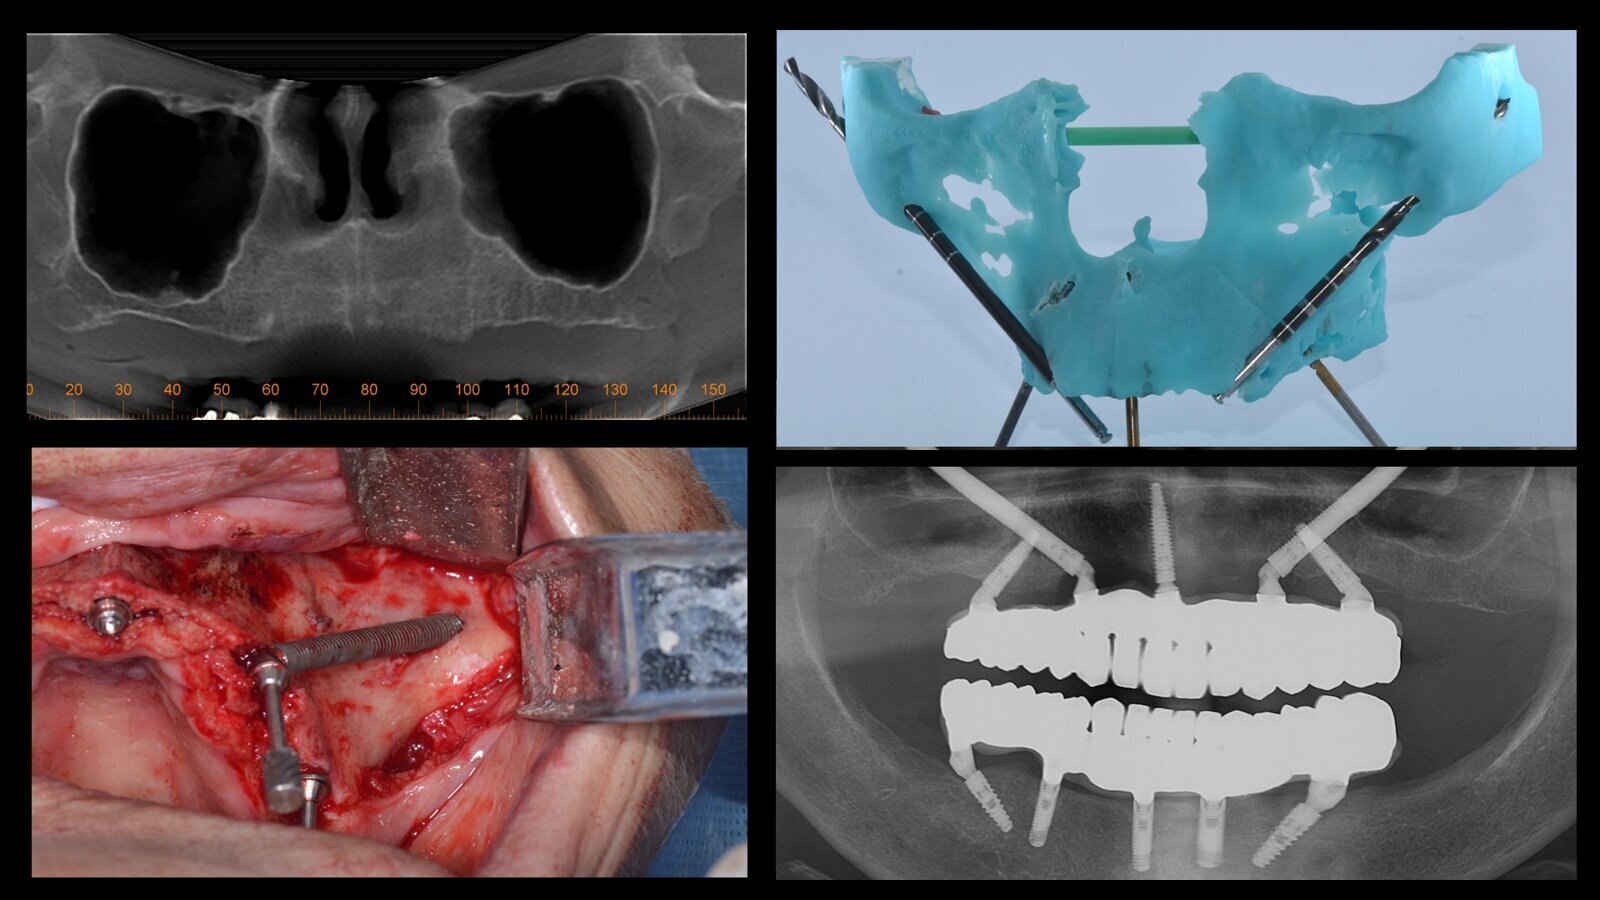

Aspecto radiográfico inicial y final y varios de los pasos realizados para la rehabilitación del maxilar con implantes cigomáticos de una paciente de edad avanzada.

Figura 2. Modelo de planificación quirúrgica.

En base a esto, se pudo realizar una distribución pentagonal de implantes para sostener 12 dientes maxilares, con dos implantes inclinados en la pared anterior del seno maxilar a nivel molar, dos implantes cigomáticos en la posición de los caninos y un implante nasopalatino en la posición de los incisivos centrales, utilizando los implantes GM Helix y GM Zygoma de Neodent.

Figura 4. Radiografía panorámica después de la instalación definitiva de la prótesis.